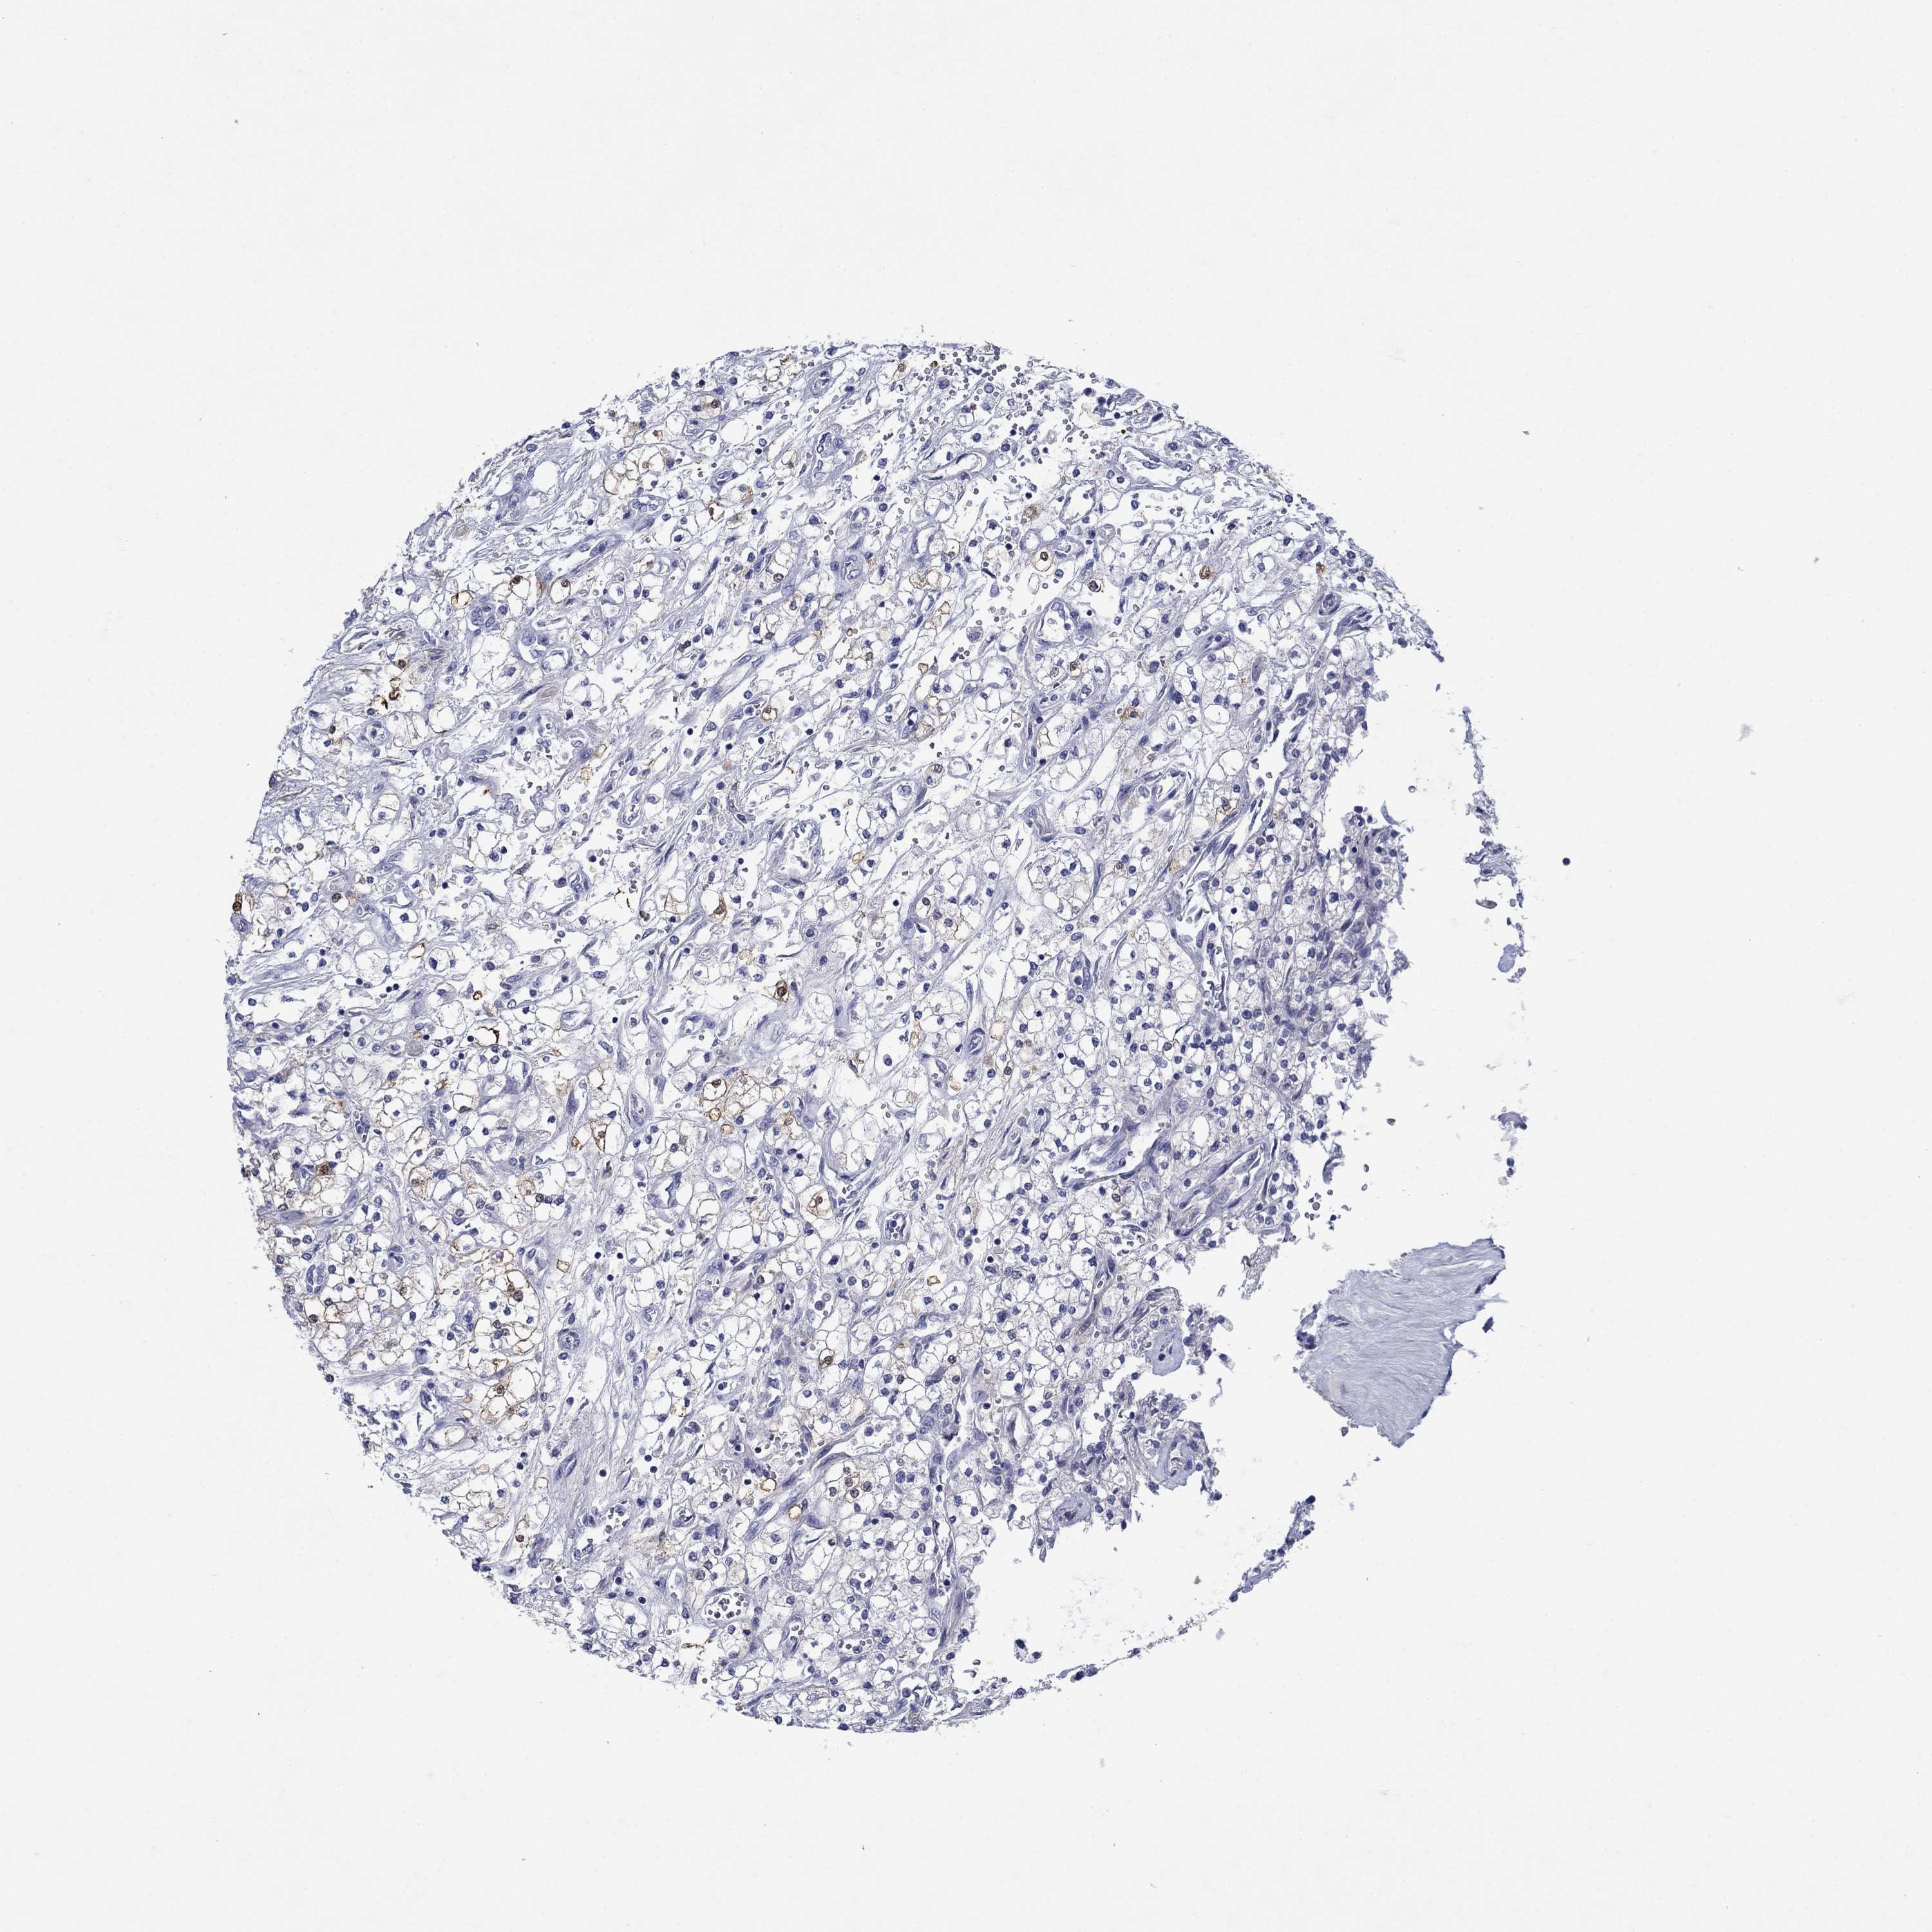

KIDNEY RENAL CLEAR CELL CARCINOMA (VALIDATION) - Interactive survival scatter ploti

The Survival Scatter plot shows the clinical status (i.e. dead or alive) for all individuals in the patient cohort, based on the same data that underlies the corresponding Kaplan-Meier plots. Patients that are alive at last time for follow-up are shown in blue and patients who have died during the study are shown in red.

The x-axis shows the expression levels (FPKM) of the investigated gene in the tumor tissue at the time of diagnosis. The y-axis shows the follow-up time after diagnosis (years). Both axes are complimented with kernel density curves demonstrating the data density over the axes. The top density plot shows the expression levels (FPKM) distribution among dead (red) and alive patients (blue). The right density plot shows the data density of the survived years of dead patients with high and low expression levels respectively, stratified using the cutoff indicated by the vertical dashed line through the Survival Scatter plot. This cutoff is automatically defined based on the FPKM cutoff that minimizes the p-score. The cutoff can be changed by dragging the vertical line or by entering a cutoff value in the square labeled "Current cut-off".

Under the Survival Scatter plot the p-score landscape (black curve; left axis) is shown together with dead median separation (red curve; right axis). Dead median separation is the difference in median mRNA expression between patients who have died with high and low expression, respectively. It is calculated as follows: median FPKM expression of dead patients with high expression - median FPKM expression of dead patients with low expression. This is intended to aid the user in visually exploring custom cutoffs and the associated p-scores and dead median separation.

Individual patient data is displayed and can be filtered by clicking on one or more of the category buttons on the top of the page. Categories describing expression level and patient information include: high, low, alive, dead, female, male and tumor stages. The scale of the x-axis can be toggled between linear and log-scale by clicking on the "x log" button. Mouse-over function shows TCGA ID, patient information and mRNA expression (FPKM) for each patient.

& Survival analysisi

Kaplan-Meier plots summarize results from analysis of correlation between mRNA expression level and patient survival. Patients were divided based on level of expression into one of the two groups "low" (under cut off) or "high" (over cut off). X-axis shows time for survival (years) and y-axis shows the probability of survival, where 1.0 corresponds to 100 percent.

SULT2B1 is not prognostic in Kidney Renal Clear Cell Carcinoma (validation)

Best expression cut offi

Based on the FPKM value of each gene, patients were classified into two groups and association between prognosis (survival) and gene expression (FPKM) was examined. The best expression cut-off refers the FPKM value that yields maximal difference with regard to survival between the two groups at the lowest log-rank P-value. Best expression cut-off was selected based on survival analysis .

When clicking on this number, the vertical dashed line indicating cut-off, the interactive survival plot, and the Kaplan-Meier curve will be adjusted to show results based on the best expression cut-off.

: 0.05

P scorei

Log-rank P value for Kaplan-Meier plot showing results from analysis of correlation between mRNA expression level and patient survival.

N/A

TCGA RNA samplesi

RNA-seq data is reported as average FPKM (number Fragments Per Kilobase of exon per Million reads), generated by the The Cancer Genome Atlas (TCGA) .

Normal distribution across the dataset is visualized with box plots, shown as median and 25th and 75th percentiles. Points are displayed as outliers if they are above or below 1.5 times the interquartile range. FPKM values of the individual samples are presented next to the box plot.

Average pTPM 1.2

Number of samples 100